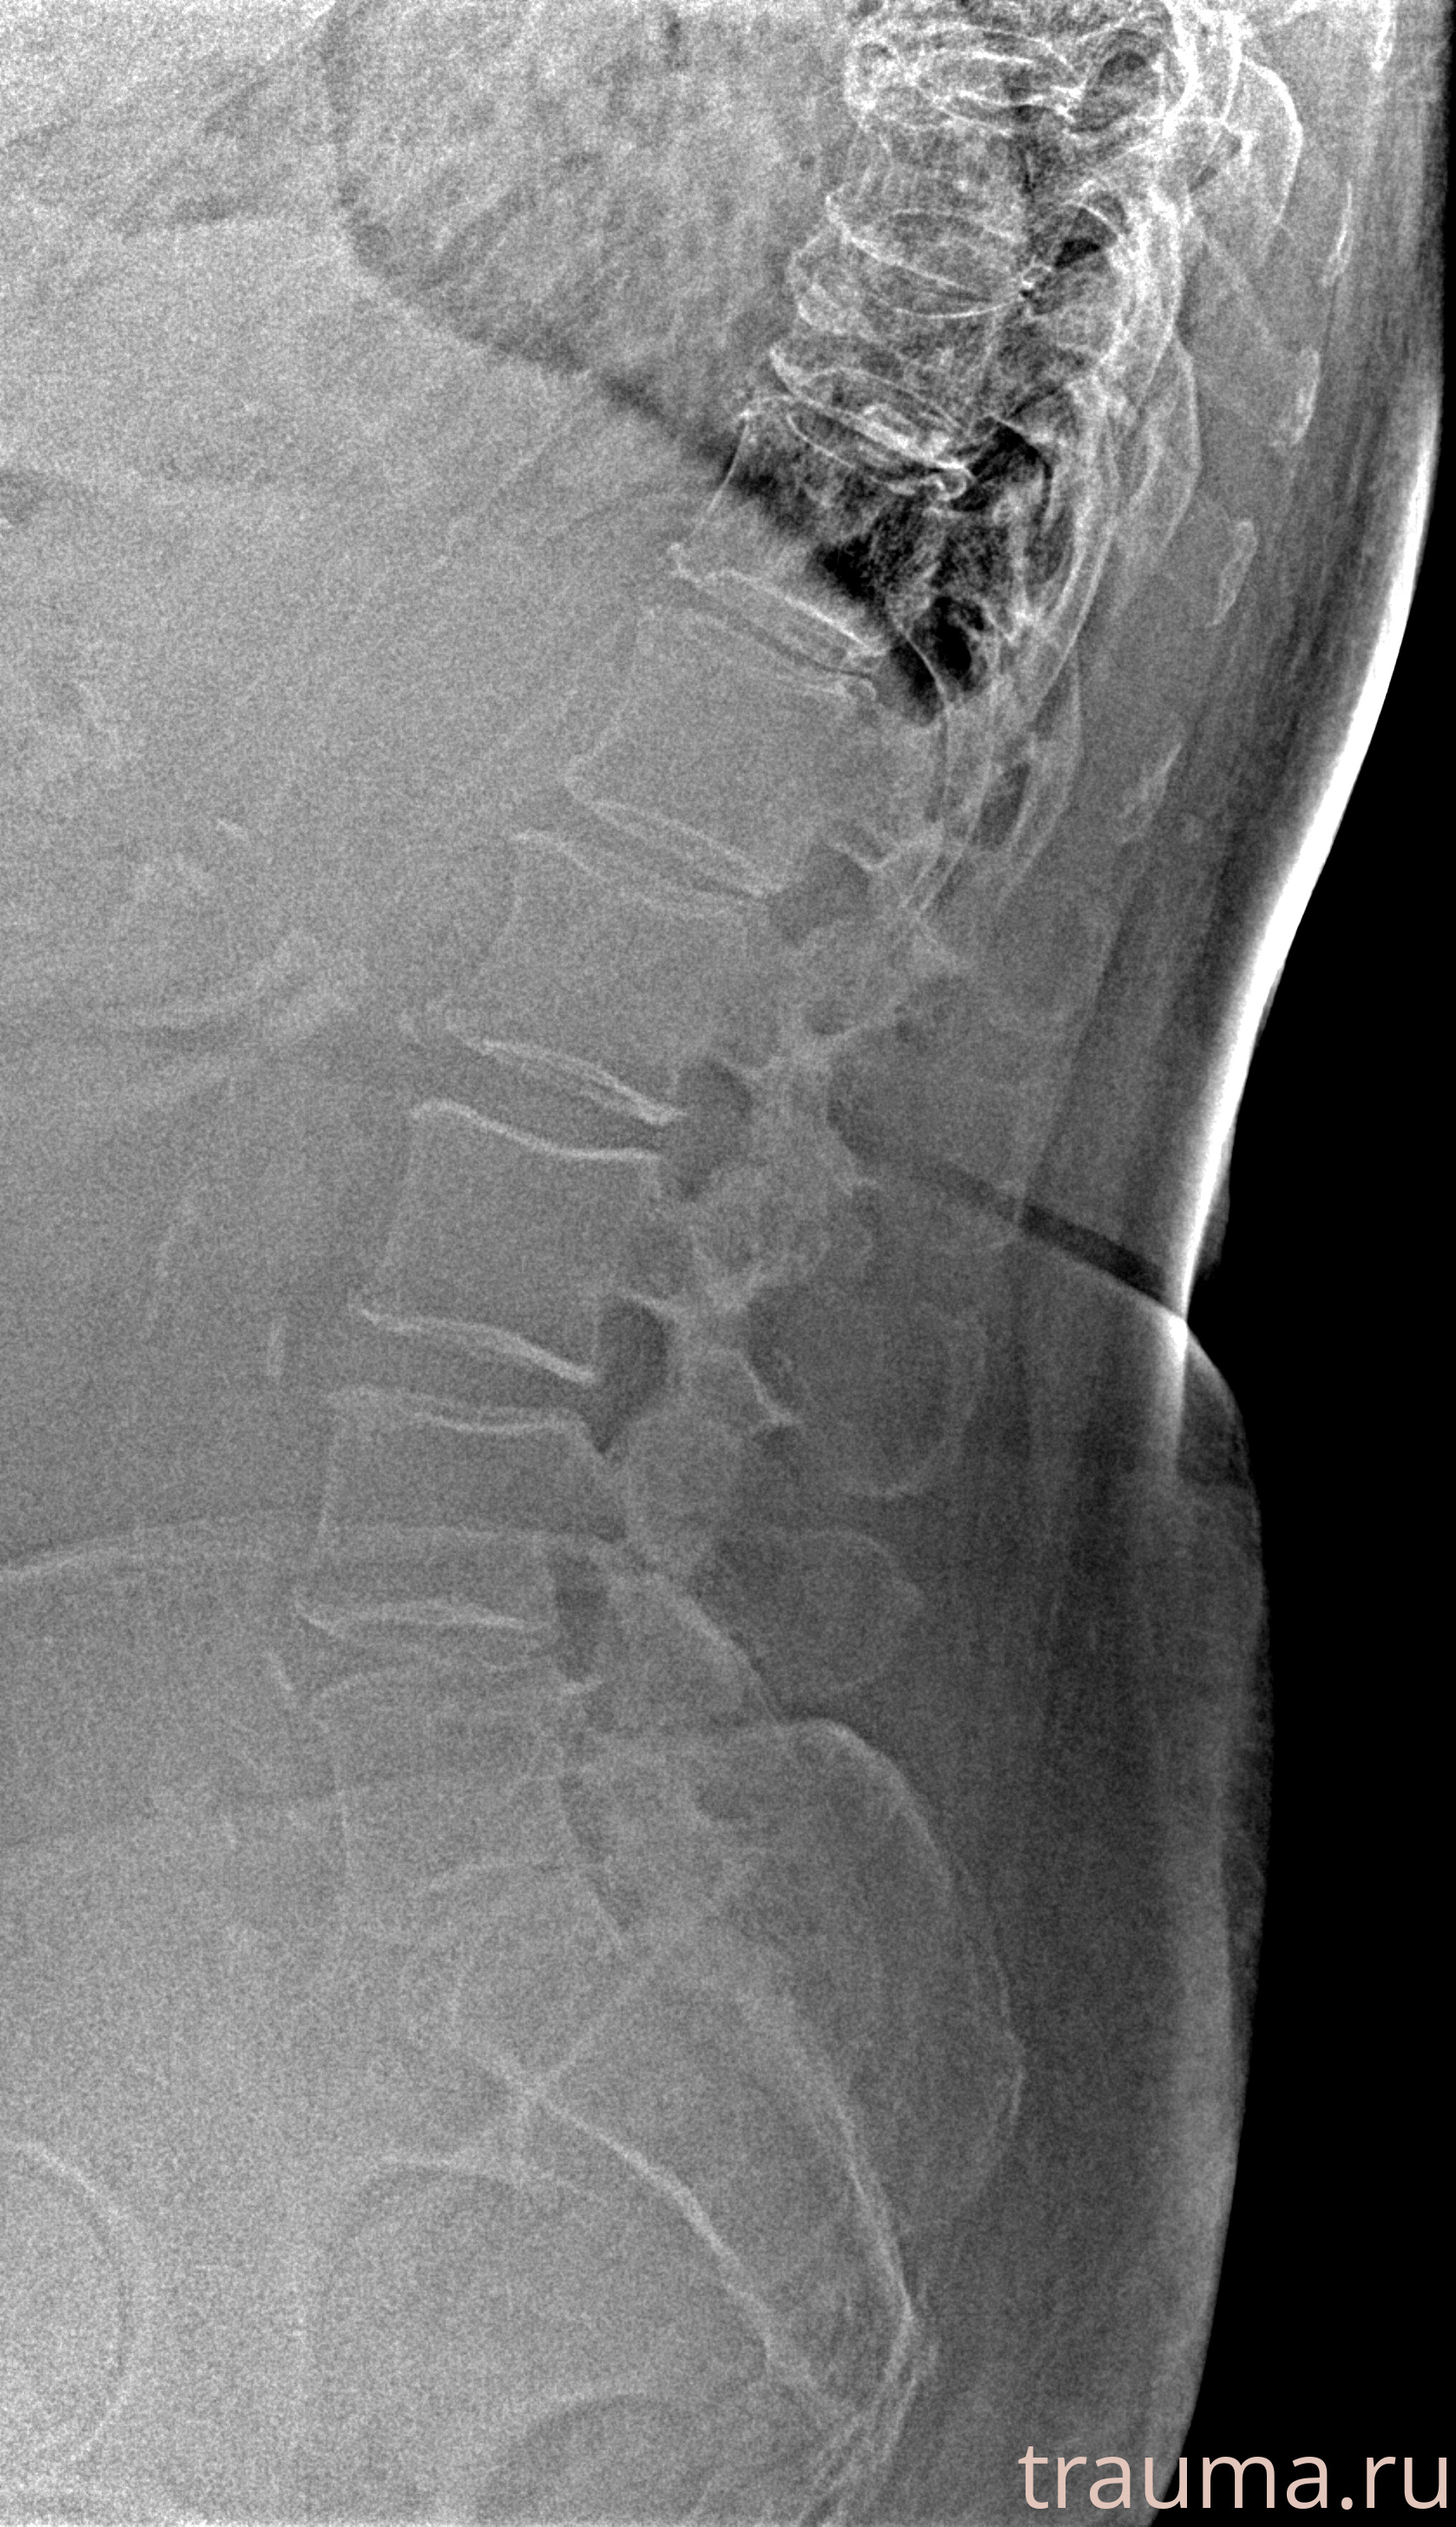

Рентген на дому: по вашему адресу приезжает врач-рентгенолог, травматолог-ортопед с мобильным рентгеновским аппаратом, проводит диагностику травмы или заболевания, делает необходимые рентгенограммы, дает рекомендации по дальнейшему лечению. Получить качественные снимки в домашних условиях возможно благодаря уникальной методике, разработанной МосРентген Центром для института  Склифосовского

при переломе шейки бедра и пневмонии от компании МосРентген Центр - партнера Института имени Склифосовского